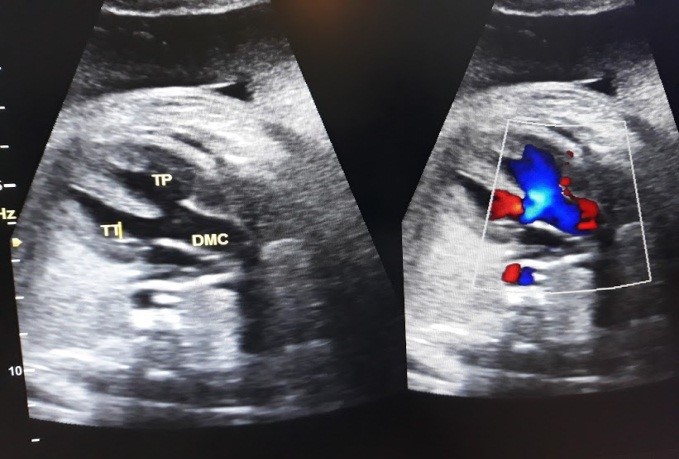

+ Siêu âm thai: Thai 27 tuần, giãn não thất, dịch màng phổi 2 bên, nghi ngờ bất thường tim, thiểu ối.

- Chẩn đoán: Đái tháo đường/thai 27 tuần nghi dị tật thai/Suy giáp sau điều trị I131.